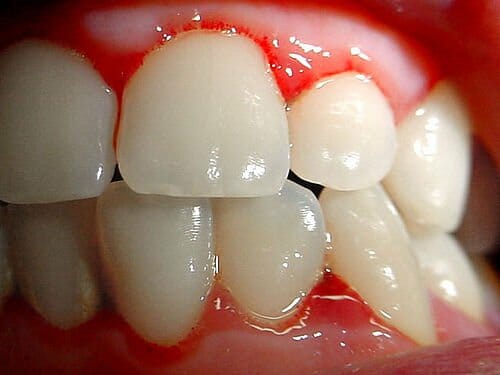

Bloedend tandvlees is veelal een pijnlijk en onaangenaam gevolg van een tandvleesontsteking. Bij bloedend tandvlees